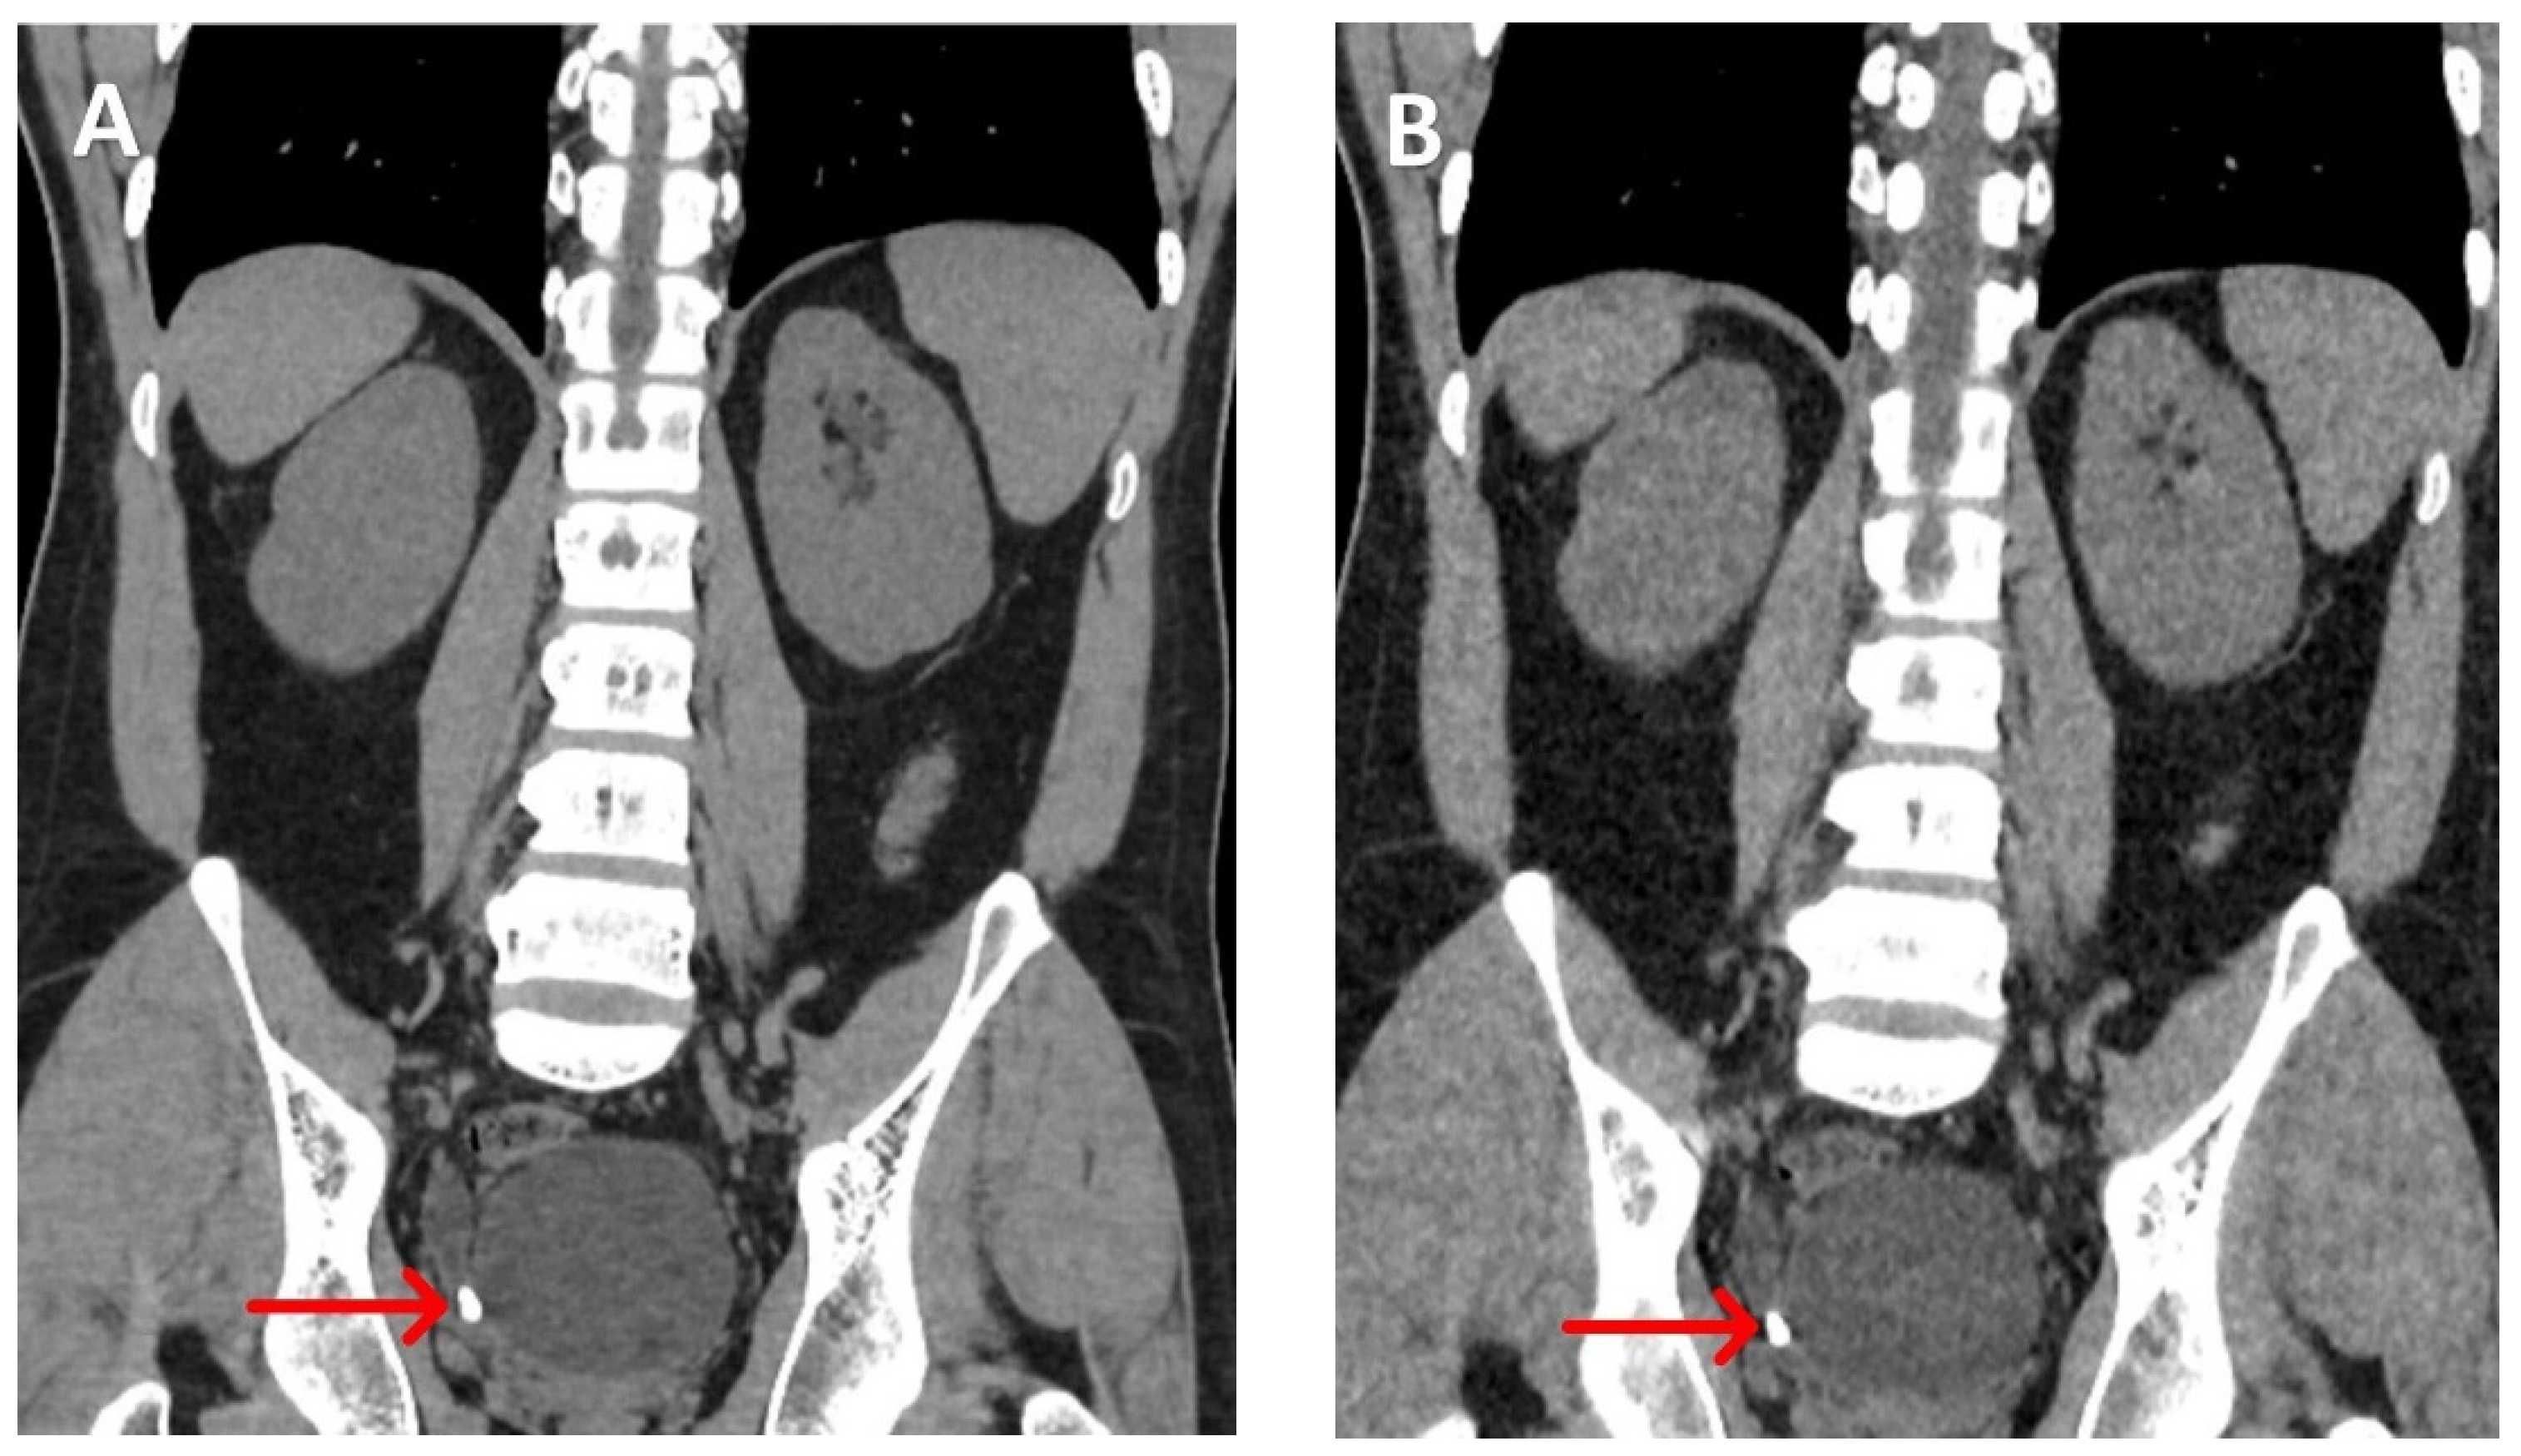

A meta-analysis has shown that LDCT-KUB can detect renal calculi > 3 mm with a sensitivity of 93% and specificity of 97%, using an average radiation dose of 1.4 mSv. This represents an approximately 85% reduction in radiation compared to the standard-dose CT-KUB (22) (Figure 1 and Figure 2).

Figure 1. A patient with small non-obstructing calculi (about 3.5 mm) in the left side middle and lower calyces. A: Normal dose CT -KUB with effective dose is 20.9 mSv. B: The low-dose protocol, with an effective dose of 2.8 mSv, shows the same calculi with good resolution.